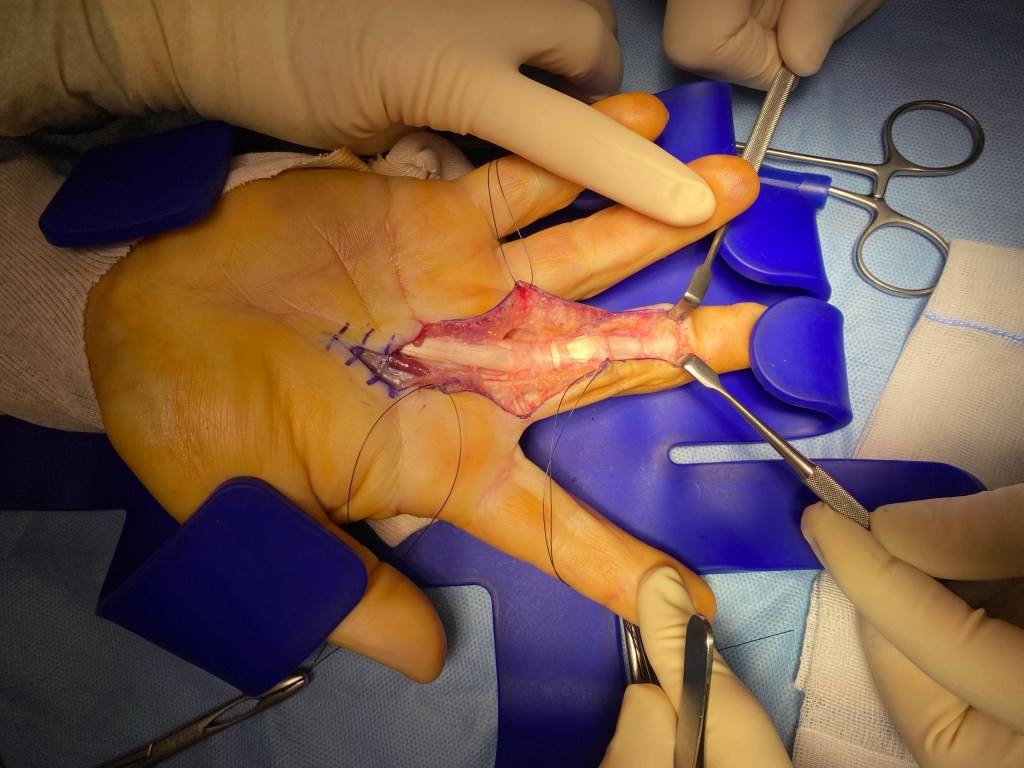

L’exploration d’une plaie consiste à rechercher des lésions des structures profondes et/ou des corps étrangers.

Elle peut être rendue nécessaire pas le caractère profond ou souillé de la plaie , des signes cliniques (saignement important , absence de sensibilité d’une zone) ou par la localisation de la plaie (la main est particulièrement riche en tendons nerfs et vaisseaux).

Pour cela, il est possible et fréquent que la plaie soit agrandie, afin de réaliser une vérification exhaustive.

L’immobilisation, si elle est nécessaire, dépend de la nature des lésions constatées et de leur réparation.